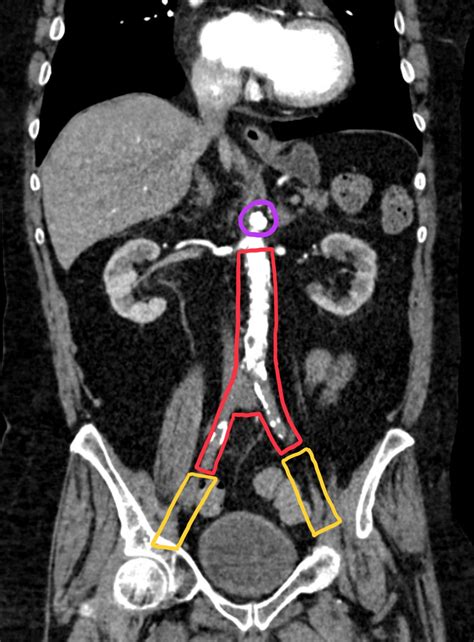

CTA / MRA Anatomic mapping Provides detailed 3D images of the aorta and iliac bifurcations.

Catheter Angiography Invasive gold standard Used primarily during intervention to visualize flow while treating the blockage.

• Endovascular Therapy: This includes balloon angioplasty and stenting. It is minimally invasive, typically involving a small puncture in the groin to access the vessel, and allows for a quicker recovery time.

• Aortofemoral Bypass Surgery: For complex, long-segment occlusions, this traditional open surgery is highly effective. A synthetic graft is used to bypass the blocked segment, ensuring a long-term, durable flow of blood to the legs.